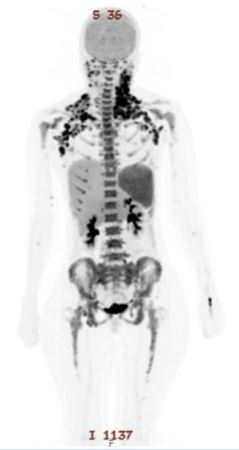

Imaging with PET-CT showed multiple FDG-avid supra- and infra-diaphragmatic lymph nodes (SUVmax 14.4) and mild splenomegaly (Figure 2). Biopsy of a right cervical lymph node confirmed T/myeloid sarcoma, with blasts positive for MPO, CD3, CD7, BCL2, and CD99, variably expressing CD5, CD117, and CD34, with focal TdT positivity and a Ki-67 index exceeding 90%. Given the high disease burden, debulking with flat-dose cytarabine (1 gram) was administered, followed by induction therapy using CALGB 10403, a pediatric-inspired ALL protocol (vincristine, daunorubicin, PEG-asparaginase, prednisone, intrathecal methotrexate and cytarabine) (9) combined with venetoclax escalated to 400 mg/day (Table 1).

Figure 1: PET-CT showed multiple FDG-avid supra- and infra-diaphragmatic lymph nodes (SUVmax 14.4) and mild splenomegaly.